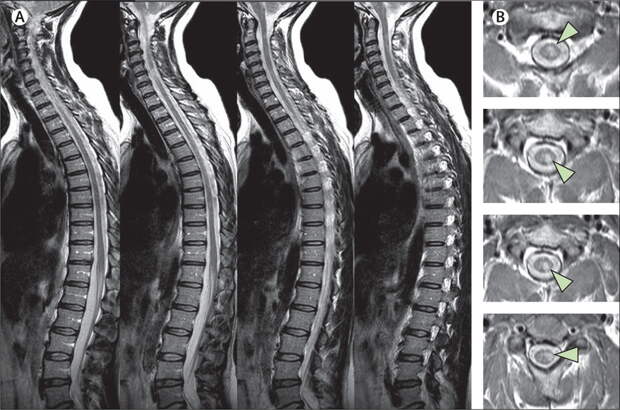

Для уточнения локализации патологии применяется МРТ грудного отдела позвоночника или КТ. Томографические способы диагностики являются самыми информативными, так как позволяют за один сеанс провести оценку состояния как плотных (костных), так и мягких тканей в зоне поражения. Скрининг проводится на специальном, высокочувствительном оборудовании.